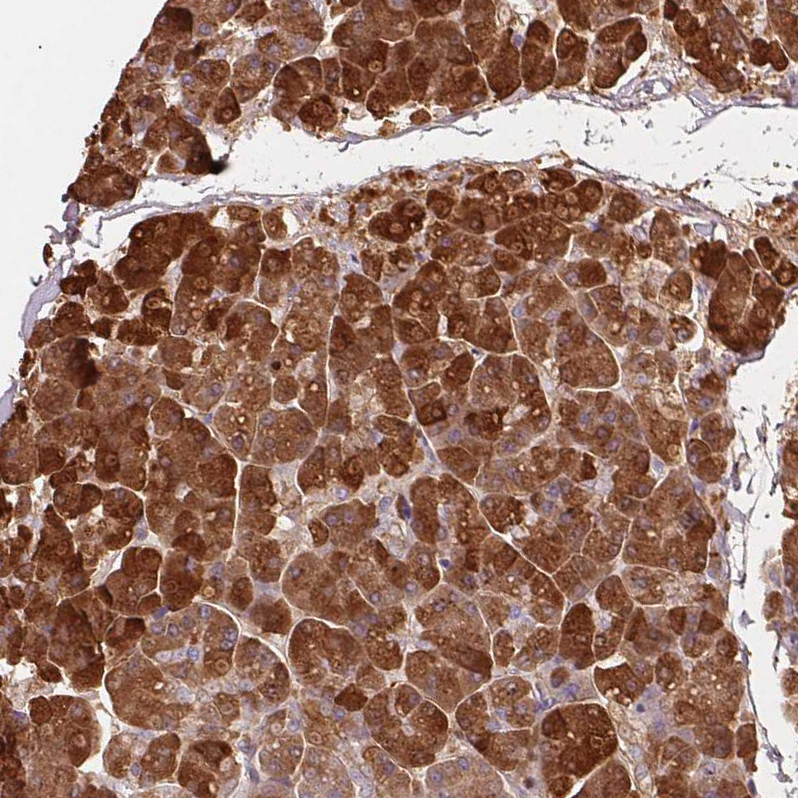

Immunohistochemistry analysis in human pancreas and cerebral cortex tissues using HPA063471 antibody. Corresponding PRSS1 RNA-seq data are presented for the same tissues.